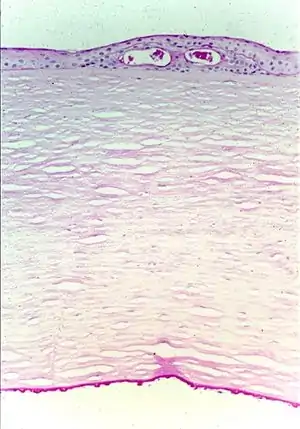

| Fuchs corneal dystrophy. Light microscopic appearance of the cornea showing numerous excrescences (guttae) on the posterior surface of Descemet's membrane and the presence of cysts in the corneal epithelium beneath ectopically placed intraepithelial basement membrane. Periodic acid-Schiff stain. From a review by Klintworth, 2009.[1] | |

FECD is a degenerative disease of the corneal endothelium with accumulation of focal outgrowths called guttae (drops) and thickening of Descemet's membrane, leading to corneal edema and loss of vision. The corneal endothelial cell layer and its basement membrane (Descemet's membrane) acts as a barrier to hydration of the corneal stroma by aqueous humor and are "pump" cells of the cornea that function to maintain hydration of the cornea at a specific level that maintains corneal stromal clarity through precise spatial arrangement of collagen fibers. In FED, Descemet's membrane is grossly thickened with accumulation of abnormal wide-spaced collagen and numerous guttae. Corneal endothelial cells in end-stage FED are reduced in number and appear attenuated, causing progressive stromal edema (swelling). Progressive endothelial cell loss causes relative influx of aqueous humor into the cornea, leading to swelling (corneal stromal edema), which results in blurred vision. Eventually, the epithelium also becomes edematous, resulting in more severe visual impairment. Focal blisters of epithelial edema ("bullae") may be particularly painful when they burst.

FECD is classified into 4 stages, from early signs of guttae formation to end-stage subepithelial scarring. Diagnosis is made by biomicroscopic examination in the clinic. Other modalities, such as corneal thickness measurement (pachymetry), in-vivo confocal biomicroscopy, and specular microscopy can be used in conjunction.

The diagnosis of Fuchs dystrophy is often made with slit lamp biomicroscopy. With direct illumination, the clinician can visualize guttae, the characteristic pathological changes in disease.